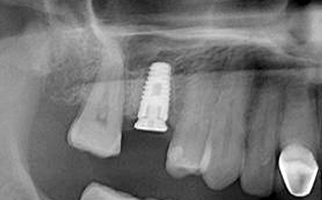

(1.) Radiograph of the missing maxillary molar and available bone between the crest and maxillary sinus.

Figure 1

(14.) Radiograph at 36 months posttreatment, demonstrating maintenance of crestal bone level and height of the augmented sinus.

Figure 14